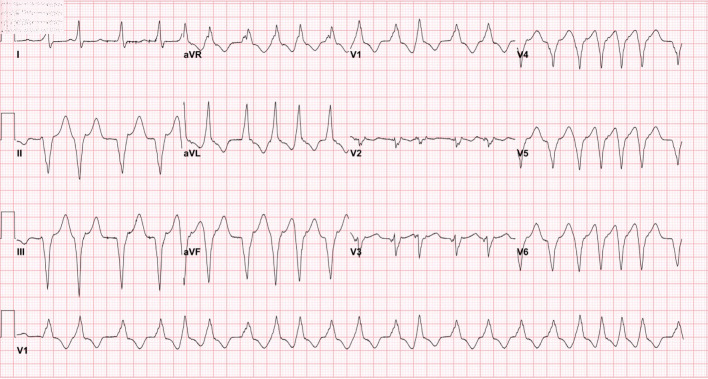

A 63-year-old female presented to a freestanding emergency room with dizziness, palpitations, and hypotension, The patient was found to have an irregular wide complex tachycardia, consistent with ventricular tachycardia, hypomagnesemia and severe hypocalcemia. The tachycardia was refractory to treatment with IV amiodarone and magnesium, and only resolved with correction of the serum calcium. Review of the medical record revealed an echocardiogram 19 years earlier reporting left ventricular dysfunction. The patient was unaware of this diagnosis and was not taking medical therapy. Echocardiogram revealed no significant change in left ventricular function, and coronary angiography showed no significant coronary artery disease. The patient's nonischemic cardiomyopathy may have been a predisposing factor for the arrhythmia presentation. We explore a hospital admission involving the rare association of hypocalcemia and monomorphic ventricular tachycardia, which is not well documented in the literature.